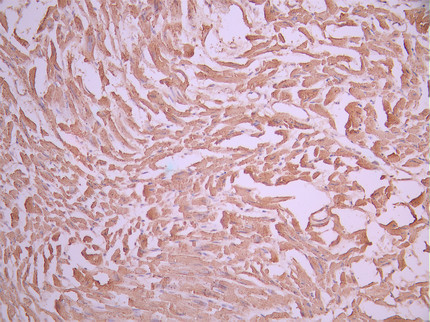

• IHC image of CSB-RA623101MA1HU diluted at 1:50 and staining in paraffin-embedded human heart tissue performed on a Leica BondTM system. After dewaxing and hydration, antigen retrieval was mediated by high pressure in a citrate buffer (pH 6.0). Section was blocked with 10% normal goat serum 30min at RT. Then primary antibody (1% BSA) was incubated at 4°C overnight. The primary is detected by a Anti-Human lgG, Fcy Fragment Specific labeled by HRP and visualized using 0.05% DAB.